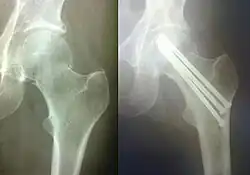

Остеоси́нтез (др.-греч. ὀστέον — кость; σύνθεσις — сочленение, соединение) — хирургическая репозиция костных отломков при помощи различных фиксирующих конструкций, обеспечивающих длительное устранение их подвижности. Цель остеосинтеза — обеспечение стабильной фиксации отломков в правильном положении с сохранением функциональной оси сегмента, стабилизация зоны перелома до полного сращения.

Погружной остеосинтез — это оперативное введение фиксатора кости непосредственно в зону перелома. В зависимости от расположения фиксатора по отношению к кости данный метод бывает внутрикостным (интрамедуллярным), накостным и чрескостным. Для внутрикостного остеосинтеза используют различные виды стержней (гвозди, штифты), для накостного — различные пластинки с винтами, шурупами, для чрескостного — винты, спицы. Нередко возможно сочетание этих видов остеосинтеза.

Внутрикостный (интрамедулярный) остеосинтез может быть закрытым и открытым. При закрытом после сопоставления отломков по проводнику через небольшой разрез вдали от места перелома вводят под рентген-контролем фиксатор. При открытом зону перелома обнажают, отломки репонируют и в костный канал сломанной кости вводят фиксатор.

Накостный (экстрамедулярный) остеосинтез производят с помощью фиксаторов-пластин различной толщины и формы, соединяемых с костью при помощи шурупов и винтов. Иногда при накостном остеосинтезе в качестве фиксаторов возможно применение металлической проволоки, лент, колец и полуколец, крайне редко — мягкого шовного материала (лавсана, шёлка).

При чрескостном остеосинтезе фиксаторы проводятся в поперечном или косопоперечном направлении через стенки костной трубки в зоне перелома.